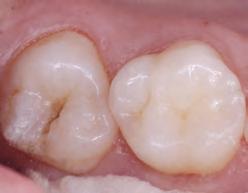

DISTO-OCCLUSAL CLINICAL CASE